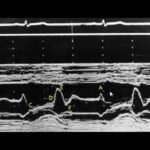

O prolapso de válvula mitral é uma alteração no funcionamento dessa válvula, que é uma das principais do coração. Essa válvula é responsável por direcionar o fluxo sanguíneo corretamente. O prolapso ocorre quando a válvula não fecha corretamente, permitindo o refluxo sanguíneo. Geralmente, é uma condição benigna e não causa problemas significativos no funcionamento do coração.

O diagnóstico de prolapso de válvula mitral começou a ser feito com mais frequência a partir da década de 80, com o uso do ecocardiograma. Esse exame de ultrassom do coração permitiu identificar o prolapso em muitas pessoas. No entanto, nem todas as pessoas diagnosticadas com prolapso necessitam de tratamento. Em casos simples, em que não há comprometimento no funcionamento da válvula, a pessoa pode levar uma vida normal e não precisa realizar repetições do ecocardiograma.